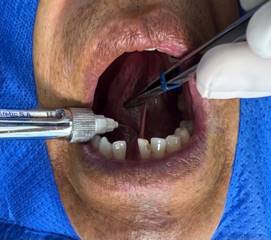

Se realiza la asepsia extraoral del paciente con Yodo Povidona (Povidyn) la cual se aplicó con una pinza hemostática con una gasa, e intraoral con Clorhexidina al 0.12% la misma que el paciente mantuvo en su boca durante 30 segundos. (Figura 2).

Figura 2. Técnica de asepsia.

Elaboración: Los autores.